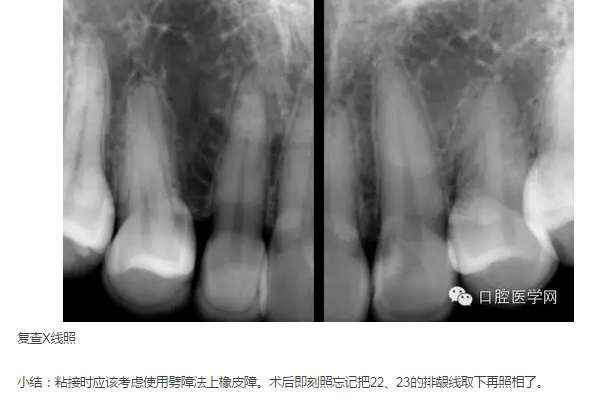

X線片示:未見13、23;14、12-22、24牙根未見明顯異常,牙槽骨約在根長2/3水平,牙槽嵴頂影像清晰。48、38近中水平阻生向分別抵于47、37遠中。

2015年5月3日:戴牙。(見圖24-30)(拍照時22、24排齦線尚未取出)